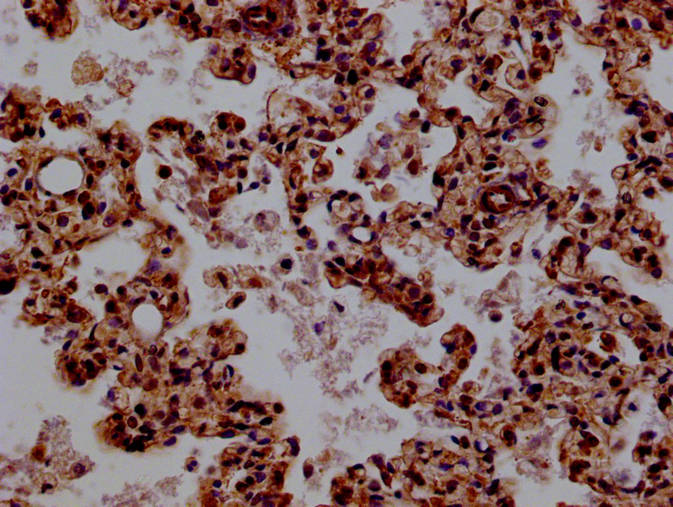

Immunohistochemistry of paraffin-embedded human lung tissue using CSB-PA872429ESR1HU at dilution of 1:100